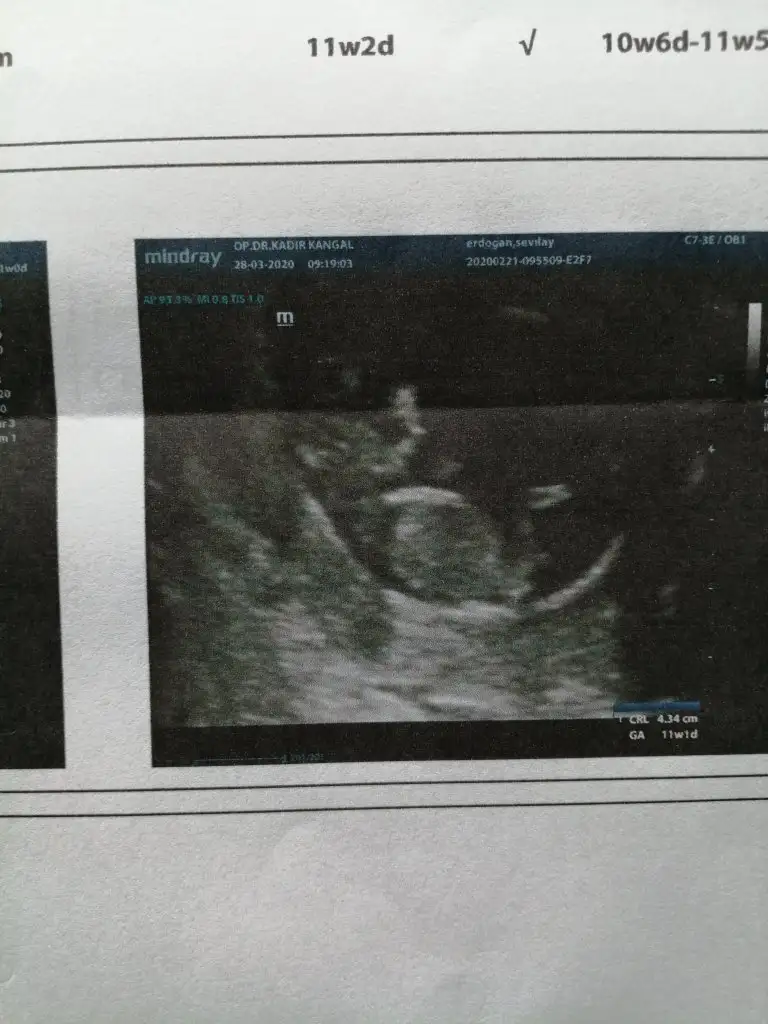

Günaydin arkadaşlar biz dün kontrole gittik 2li test için 1hafta sonra sonuç çıkacak yaptırıp sonuç alan oldu mu

• IMG_20200328_092901.webp

IMG_20200328_092901.webp

47 KB · Görüntüleme: 35

Günaydın canım. Ben yaptırdım geçtiğimiz hafta sonucum güzel çıktı 10 bin de bir dedi risk için doktorum iki ayrı bebek için ayrı ayrı yapıldı. Hayırlı sonuçlar olsun inşallah 🤲